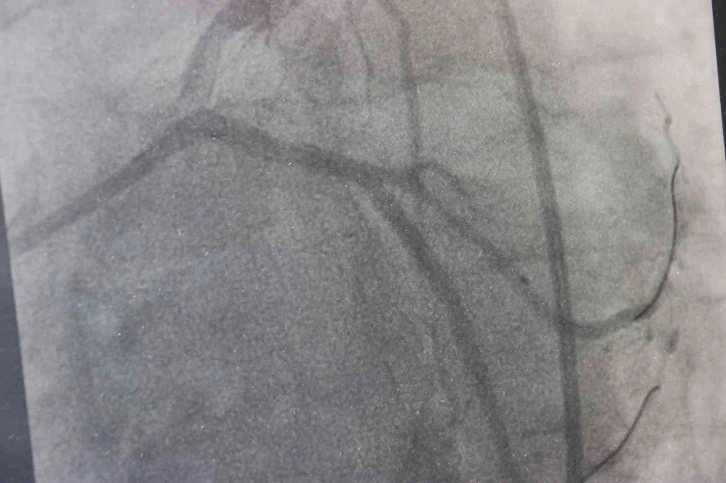

Trans yağların özelliklerinden dolayı endüstride son derece rağbet gördüğünü aktaran Doç. Dr. Akdağ, “Biz, istemiyoruz. Çünkü trans yağlar insan vücudundaki doğal yağ grubundan çok farklı. Trans yağlar özellikle damarın endotel dediğimiz en önemli kısmını bozan bir madde. Dolayısıyla trans yağlar damar yapılarını bozduğu için başta kalp ve beyin olmak üzere vücudun birçok organına zarar vermekte. Bununla beraber birçok kanserin oluşumuna yol açabilmekte. Obeziteye, şeker ve kolesterol değerlerimizi artırabilmekte. Bu nedenler dolayı biz, trans yağların kullanımını istemiyoruz. Trans yağlar 1911 yılında maalesef hayatımıza girdi. O günden bugüne giderek tüketimi artmakta” dedi.